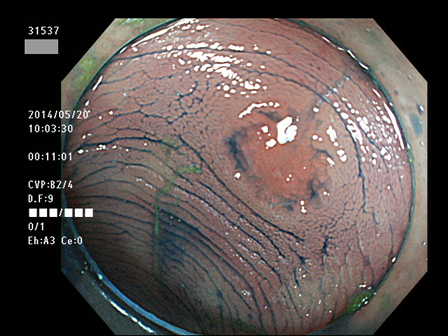

上記100名より抽出した平坦・陥凹型腺腫(=癌化の危険が高いが見落としやすい病変)の内視鏡写真

31532 31533 31534(SSA/Pのみ) 31537 31538 31539 31540 31541 31542 31545 31546 31550 31552 31553 31554 31555 31556 31562(SSA/Pのみ) 31563 31564 31565 31566 31567 31572 31573 31574 31576 31578 31579 31580 31581 31582 31586 31587 31589 31590 31591 31593 31596 31597 31598 31599 ・・・・の65名